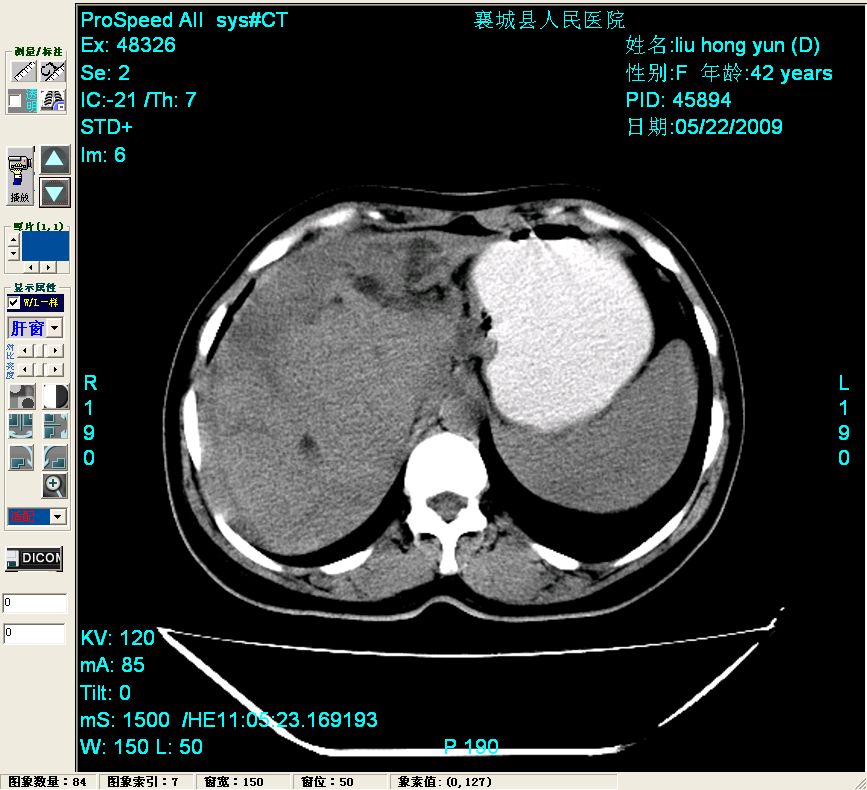

平扫:

平扫左肝外叶体积显著减小,左肝外叶见多房囊性低密度区,左肝实质及右肝前叶浅表实质呈低密度改变,左肝及右肝前叶胆管扩张,脾大

胰头部见结节状高密度影,其前方略可分辨扩强胆部管,平扫到增强始终有,但现在尚难与胃肠造影剂鉴别.

结合病史考虑,1现在引起黄疸体征的原因应该是胆总管胰段结石阻塞,建议局部胃肠造影剂排空后复查.

考虑:1、胆道结石伴肝内胆管扩张、积气;胆系感染!2、从平扫、增强片来看,不存在胆管肿瘤征象;3、提介建议:作为影像医师,在做一项检查之前应先熟悉临床医生的目的,象这个病例,检查前就不应喝高密度造影剂,而应充分喝好水就可,要不适得其反,反而较难判断胆总管下段是否有结石。